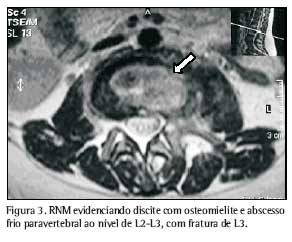

Através da tomografia computadorizada, foram evidenciadas irregularidade e redução do espaço articular entre L2 e L3, associadas à esclerose dos corpos vertebrais correspondentes, e fratura em L2. O disco vertebral entre L5 e S1 apresentava leve protrusão, sem causar repercussões intra-raquianas significativas. Os achados sugeriram a possibilidade de processo inflamatório e/ou infeccioso, acometendo os corpos vertebrais L2 e L3, bem como o disco intersomático correspondente (Figura 1). A ressonância nuclear magnética evidenciou redução do espaço discal L2/L3 e abscesso frio na área correspondente, o que reforçou a possibilidade de processo do tipo espondilodiscite (Figuras 2 e 3).

A ressonância magnética é o método de imagem mais sensível e mais específico na diferenciação da natureza dos colapsos vertebrais, além de mostrar alterações precoces(9,18,19) para o diagnóstico de espondilite por tuberculose(20), apesar de poder encontrar imagens semelhantes por germes piogênicos e neoplasia vertebral(9, 21).

A redução do espaço intervertebral é atípica( 20, 22) em infecções piogênicas. Porém, as imagens apresentadas por esta paciente, de redução intervertebral associada ao envolvimento de vértebras consecutivas, são consideradas características de espondilite tuberculosa(9).